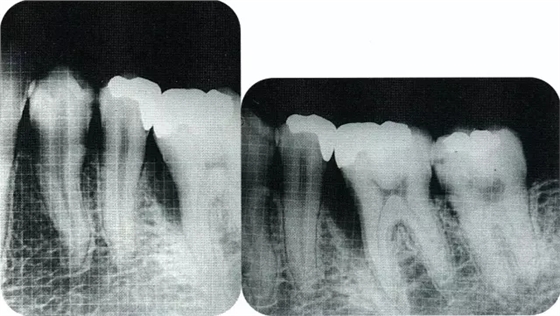

▲圖7-1左下6近中可觀察到3壁性垂直性骨缺損。此病例考慮到齦瓣供血關(guān)系,在前磨牙部位進(jìn)行了減張切開,沒有進(jìn)行縱切開。并利用刮治器、牙周外科用車針進(jìn)行了徹底的骨缺損部位搔刮。

▲圖7-2術(shù)前x片。確認(rèn)存在垂直性深骨缺損。